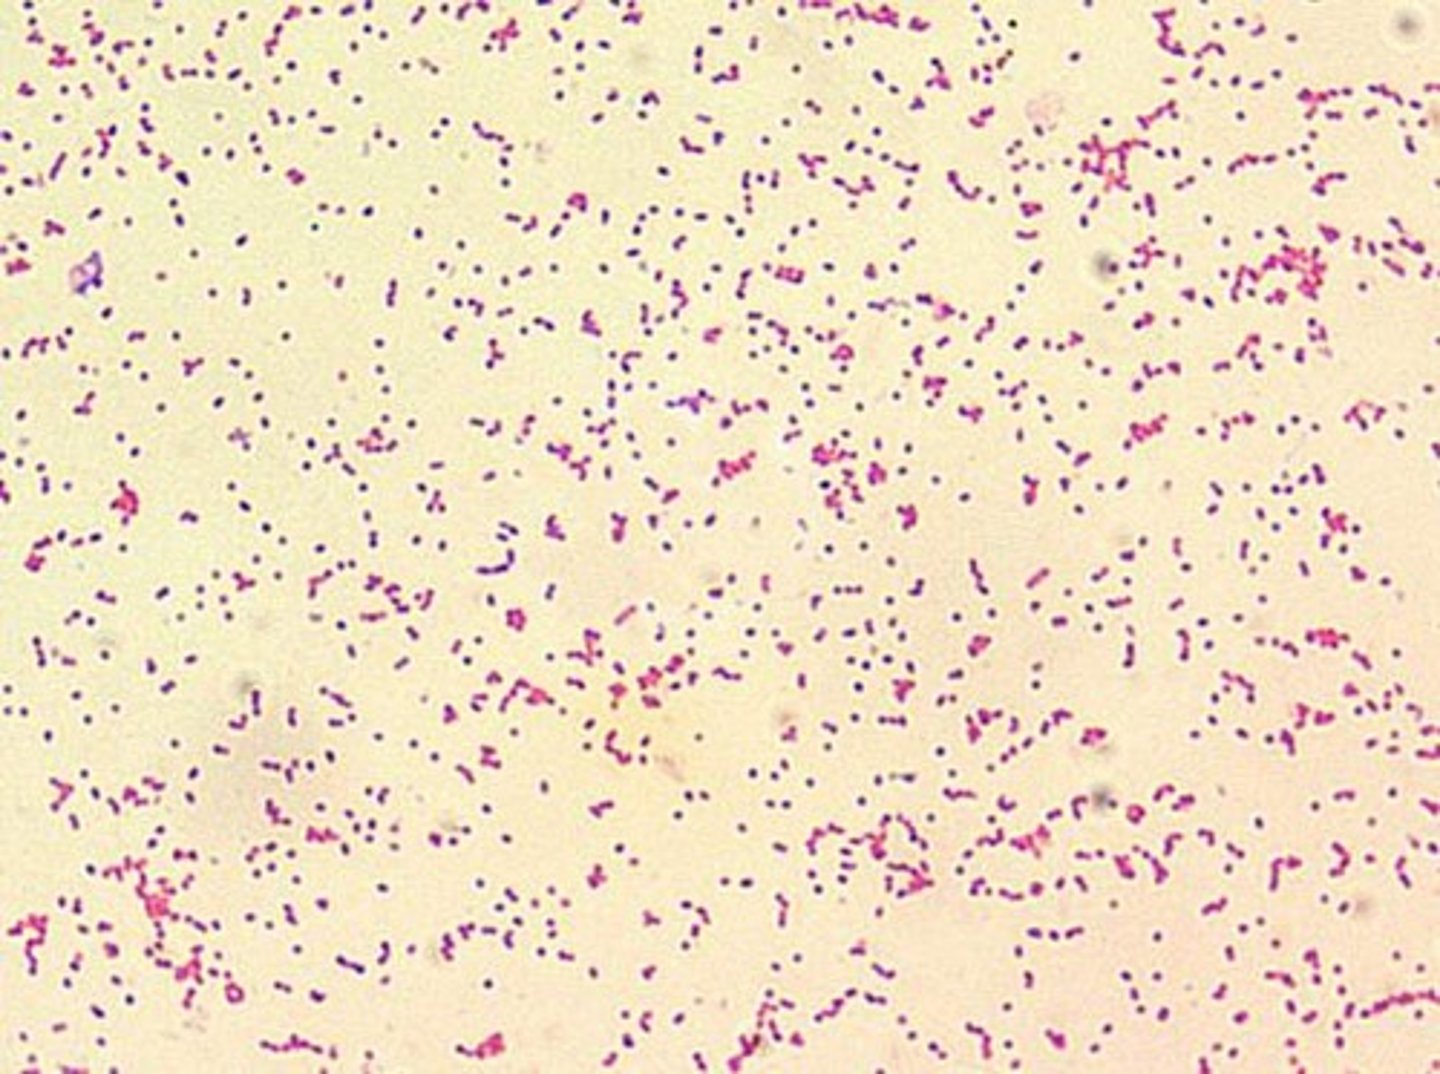

Escherichia coli (E. coli)

Gram negative rods

Affects the urinary, gastrointestinal, and reproductive systems

Causes acute UTIs, diarrhoea, and uterine infections